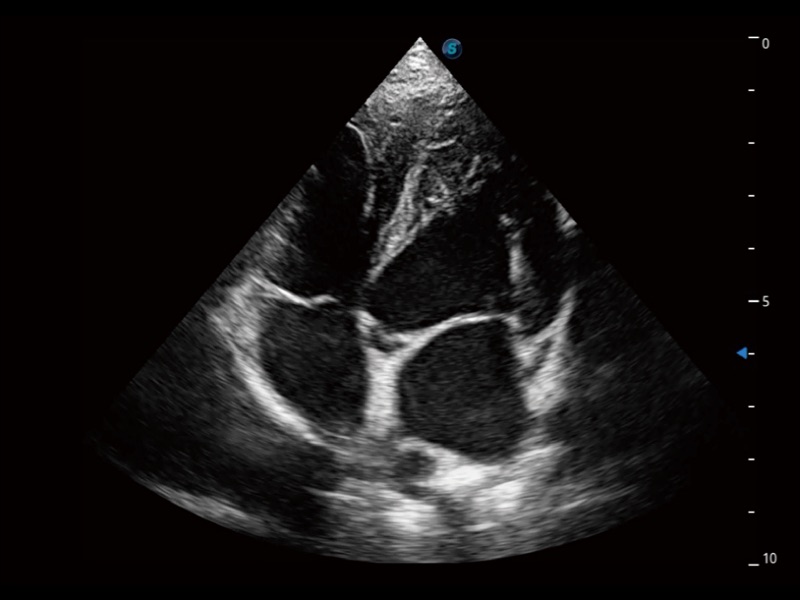

能够基于左心室壁追踪和辛普森法,自动计算射血分数,支持多个可移动点描迹,与手动测量相比,极大节省了动物医生的时间和精力。

实时用颜色表示心肌组织运动,观察和定量组织的运动情况,对快速检测与评估心肌的灌注和活性、电传导及心肌收缩和舒张功能等均能提供重要的诊断信息。